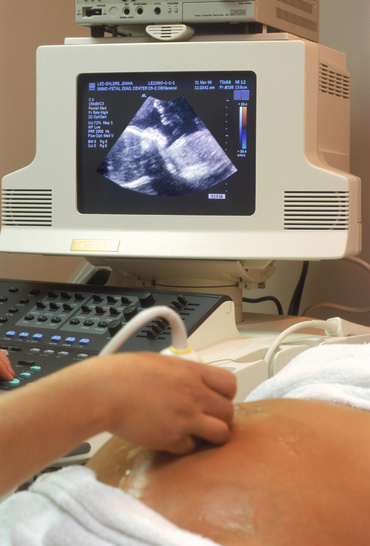

Cate ecografii sunt recomandate in timpul sarcinii si de ce

Pe parcursul unei sarcini normale, fara probleme sunt necesare un numar minim de patru ecografii. Vom vorbi acum despre fiecare dintre ele, aratand cand anume se efectueaza...

Nimic nu este mai emotionant decat prima ecografie a sarcinii, cand ai confirmarea oficiala ca esti insarcinata si, in functie de momentul in care o faci, auzi si pentru...